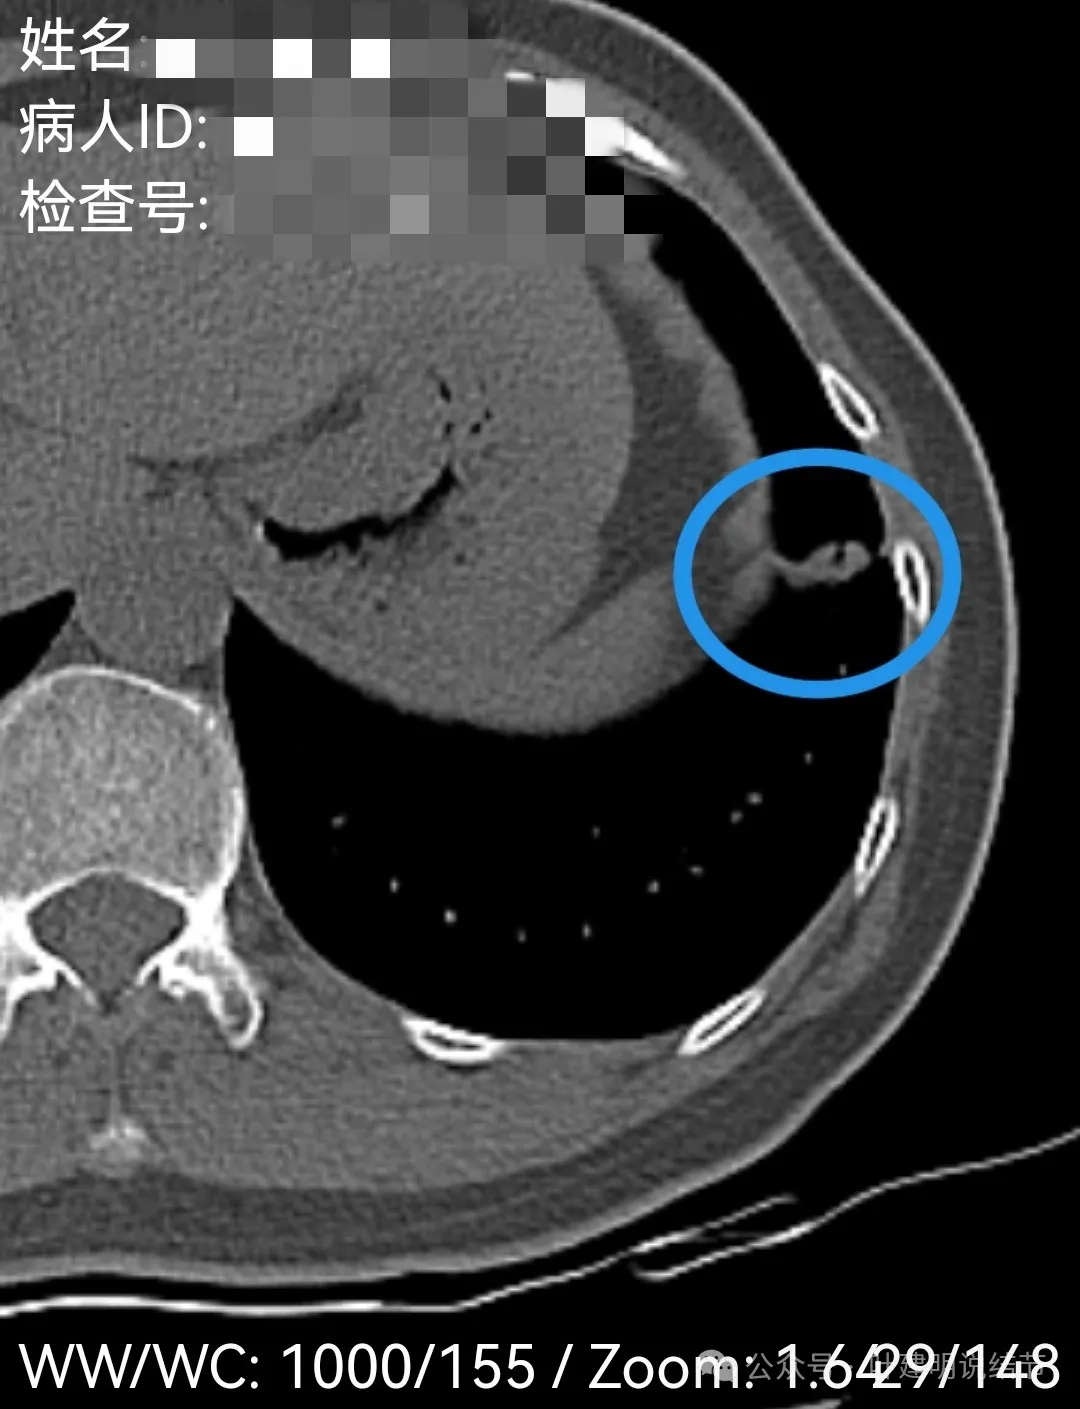

左下叶主病灶实性,收缩力较弱,胸膜略有牵拉,表面似乎较为光滑,毛刺不明显,血管征不明显,整体密度显得较高。

纵隔窗可见。

局部放大了看,边缘略毛糙;胸膜略牵拉;灶内有小区域密度偏低的空泡或偏低密度区;表面似有较为勉强的分叶征的样子。但整体说不上明显收缩力,磨玻璃成分也不大明显。